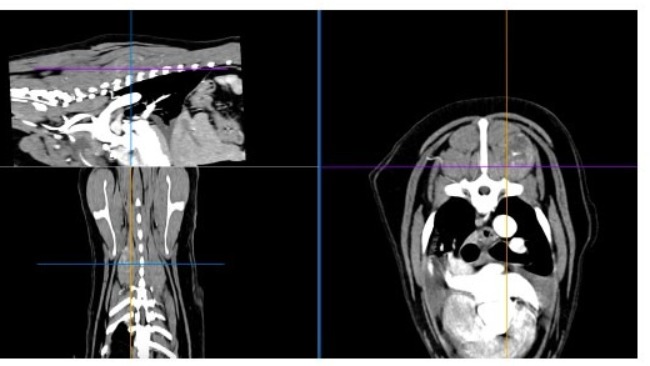

Chłoniak jest w częściowej remisji. Pozostaje płyn w jamie opłucnej oraz guz w śródpiersiu, który będzie diagnozowany. Kontynuacja leczenia za dwa tygodnie.

We wrześniu 2025 badania profilaktyczne wykazały duże nieprawidłowości w organizmie Atenki. Pomimo początkowych wątpliwości kompleksowe badania potwierdziły chłoniaka T-komórkowego, tego bardziej agresywnego.